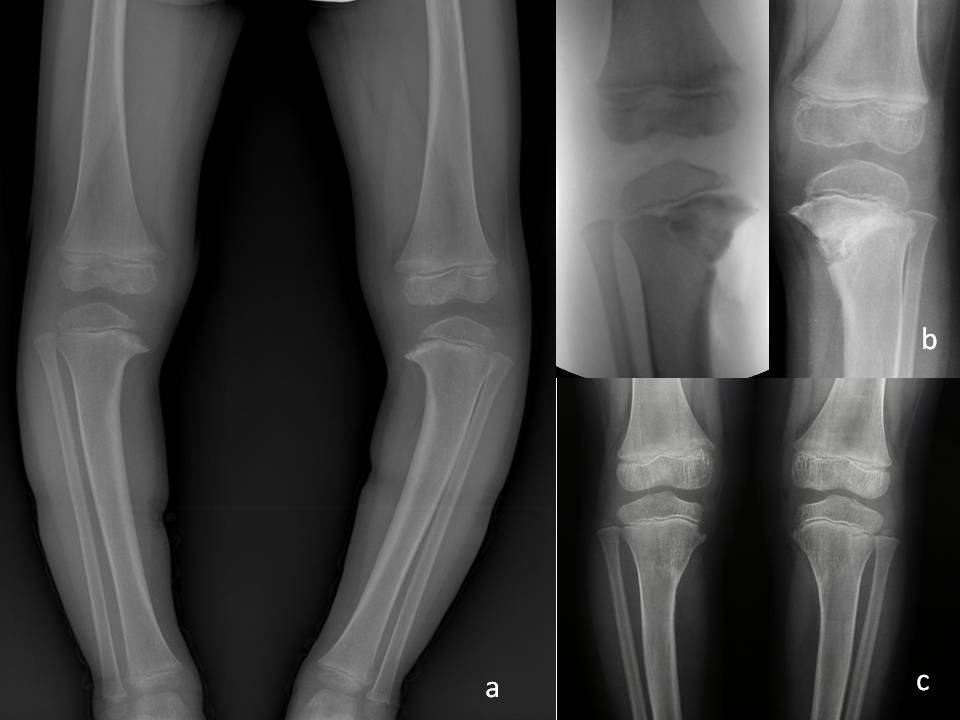

fig 14

Fig. 14: A) Aspetto radiografico del paziente in fig 13. B) Intervento di osteotomia di sollevamento del piatto tibiale bilaterale. C) Controllo RX dopo 2 anni.